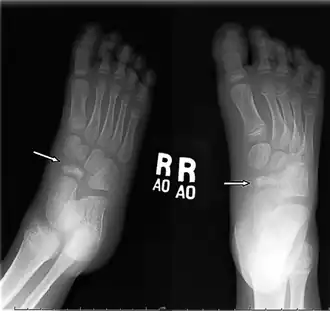

Diagnosis is made on the basis of history and a high index of suspicion. On examination there is tenderness to palpation on navicular head. Radiographs reveal typical changes of increased density and narrowing of the navicular bone.An X-ray of both feet is used to diagnose disease.